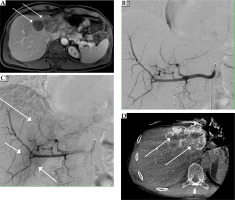

Fig. 2

The same patient as in Figure 1, with confluent colorectal liver metastases in the left liver lobe. A) Pre-interventional MRI shows inhomogeneous Gd-EOB-DTPA enhancement of the metastases (arrows) in the left liver lobe (dynamic T1 axial in portal venous phase). Coeliacography with contrast-enhanced common hepatic artery early (B) after injection. Later (C), there is a very faint blush in the region of the left liver lobe (arrows), which corresponds to the metastases. Cone-beam-CT (D) was performed from the common hepatic artery with visualization of the hypovascularized target tumor in the liver segments II and IVa (arrows) for transarterial chemoembolization planning